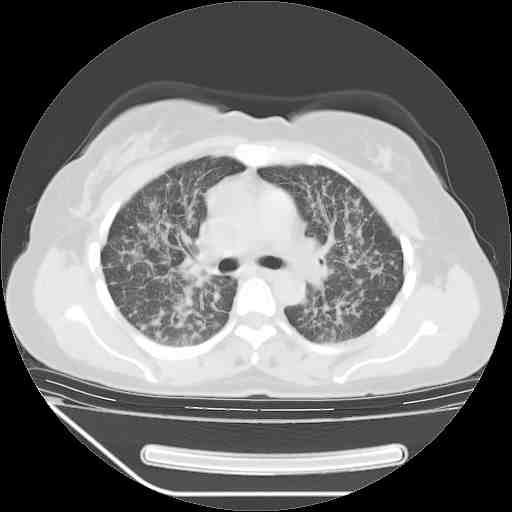

f50,肺ca治疗后,做过穿刺,确诊是肺ca,大家看看这是去年12月做的

考虑  腺癌肺内转移,治疗较前病灶缩小、减少

支持肺癌并肺内淋巴管转移,

肺癌并肺内转移,这种疾病治疗后在影像上看略有好转,不是很显著,但是肿瘤治疗效果影像只是一方面。

支持肺癌并肺内淋巴管炎,  原发灶小了,但转移较前片明显了.

支气管血管束粗而乱,考虑肺癌肺内淋巴管转移,右侧乳房第一二层软组织成份较左侧多,不会有问题吧?

支持右肺下叶周围型肺癌并肺内淋巴管炎,  原发灶小了,但转移较前片明显了.。

标准的细支气管肺泡癌呀!治疗后病情有所控制,也没治愈的迹象!